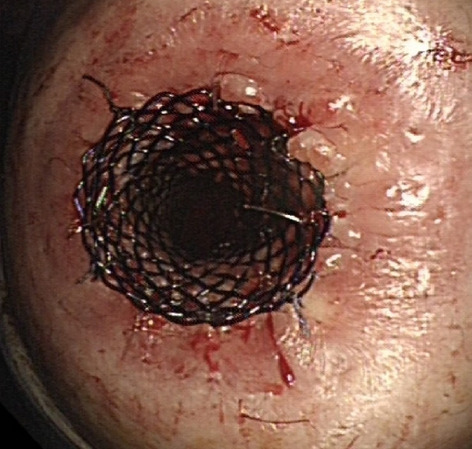

Methods: Analysis of our prospectively collected, IRB approved database of hybrid, open, and robotic esophagectomies was performed. Starting 01/2019, we implemented an updated robotic standardized anastomotic technique using a circular stapler and ICG (indocyanine green) for our RAMIE cases at our academic center (Picture 1). Outcomes of patients undergoing this standardized robotic Ivor Lewis esophagectomy for esophageal cancer from 01/2019 – 11/2020 were compared to our overall cohort from 06/2016–06/2020 (Hybrid/Open group).Propensity score matching comparing robotic to hybrid procedures will be performed and data will be presented upon the meeting.

Results: A total of 615 patients were analyzed. A total of 96 patients underwent a robotic assisted Ivor Lewis esophagectomy. Of these, a total of 56 patients underwent a robotic thoracic reconstruction using the updated standardized circular stapled anastomosis. A total of 64 patients were operated using an open approach and 455 underwent a hybrid procedure with a circular stapled anastomosis (Hybrid/Open group). Demographic and oncological data is shown in Table 1. Mean age was 63 years (range 46–80) in the robotic group and 63 years (range 33–91) in the hybrid/open group. Further details about postoperative complications are depicted in Table 2. One patient developed an anastomotic leak in the robotic group, resulting in an anastomotic leak rate of 1.8%. In comparison 63 patients (12%) developed an anastomotic leak in the Hybrid/Open group (p = 0.0132). Median length of stay (LOS) was 13 days in the robotic group (range 7–52), compared to a median LOS of 15 days (range 9–99) in the open/hybrid group.

Conclusion: A standardized circular stapled anastomosis in RAMIE cases for esophageal cancer may result in very low anastomotic leak rates and thereby positively influence outcomes in selected esophageal cancer patients.